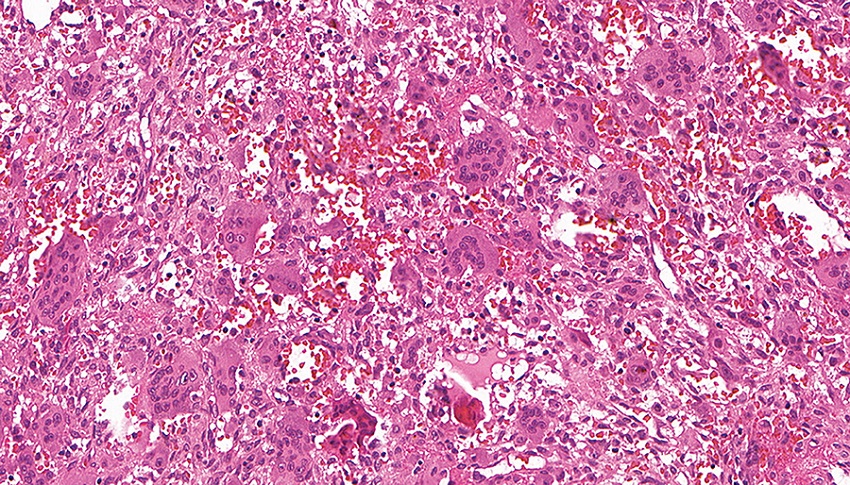

Photomicrography highlighting the proliferation of mononuclear mesenchymal cells associated with a population of multinucleated giant cells in a matrix of fibrous connective tissue and extravasated red blood cells (HE, 40×) HE: hematoxylin and eosin.